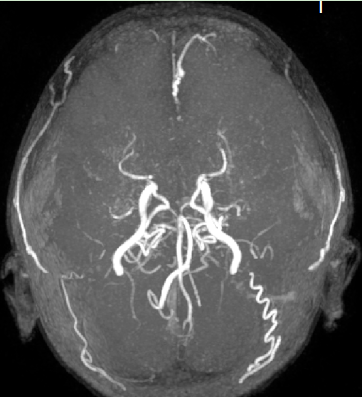

弥散加权mramri 提示右侧大脑半球大面积脑梗死,右侧大脑中动脉闭塞